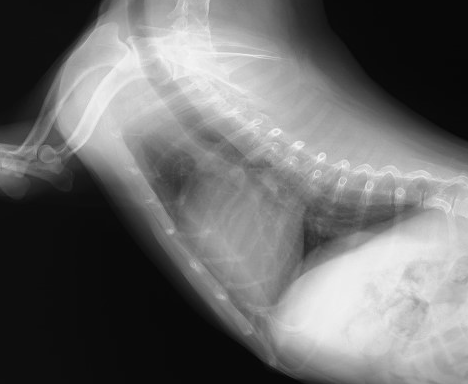

僧帽弁閉鎖不全症のため呼吸困難で来院した犬のレントゲン写真です。心臓が明らかに大きくなって、心臓より後ろの肺が白くなって十分に膨らまなくなっているのがわかります。鬱血性心不全による心原性肺水腫の典型的なレントゲンになります。このままの状態では命の危険がある状態です。